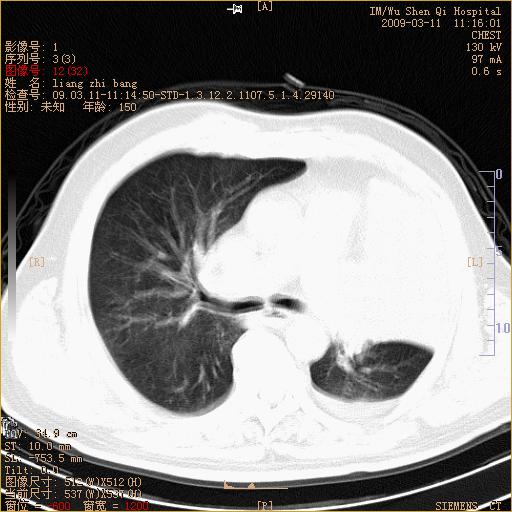

标题: CT18604:男,60岁,咳嗽一月余 [打印本页]

标题: CT18604:男,60岁,咳嗽一月余

1)考虑左肺上叶中央型肺癌并左肺上叶肺不张;建议必要时行纤支镜检查进一步明确诊断。2)左侧胸腔积液。

考虑左肺上叶中央型肺癌并左肺上叶肺不张

肺门肿块、支气管开口闭塞伴肺不张及胸水!典型的中心型肺癌变现!

1、左肺上叶中央型肺癌并上叶阻塞性肺不张。

2、左侧胸腔少量积液,右侧胸膜轻度增厚。

左肺们肿块并左肺上叶不张。考虑左肺中心性肺癌并左肺上叶不张及左侧胸腔积液